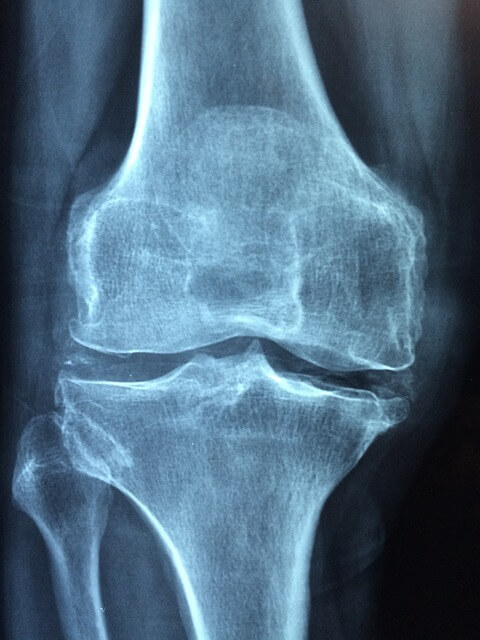

뼈를 연결하고 움직임을 가능하게 하는 관절은 문제가 발생할 때까지 그다지 눈에 띄지 않는 것이 특징입니다. 결국 불편함이나 통증을 느끼고 나서야 이상이 생겼음을 인지하게 됩니다.

관절 건강을 위한 방법을 이해하려면 관절의 복잡한 해부학적 구조를 먼저 알면 도움이 됩니다.

■ 관절은 두 개 이상의 뼈가 만나는 지점으로 무릎 및 팔꿈치와 같은 경첩 관절, 엉덩이와 어깨에 있는 볼-소켓 관절, 목에서 볼 수 있는 피벗 관절, 손목의 활주 관절 등이 있습니다.

■ 관절 건강의 핵심은 뼈 끝을 덮고 있는 연골에 영양을 공급하는 투명하고 점성 있는 액체인 윤활액이라고 할 수 있습니다. 이 윤활핵은 천연 충격 흡수 장치 역할을 하여 마찰을 줄이고 관절 표면의 마모를 방지하며 관절의 움직임을 보다 부드럽고 원활하게 하고 부상 위험도 최소화 해줍니다.

■ 연골은 관절 내에 있는 뼈의 끝부분을 덮는 완충재 역할로 뼈가 미끄러질 수 있는 매끄러운 표면을 제공하여 마찰을 줄이고 무게를 고르게 분산시킵니다. 나이가 들어도 통증이 없는 부드러운 관절 이동성을 위해서는 건강한 연골이 큰 역할을 합니다.

■ 인대는 뼈와 뼈를 연결하고 힘줄은 근육을 뼈에 연결합니다. 이러한 결합 조직은 움직임에 안정성을 제공하고 원하는 대로 움직임을 제어할 수 있게 합니다. 관절을 둘러싸고 있는 강하고 상태가 좋은 근육은 지지와 보호를 제공해 관절의 안정성을 유지하는 데 중요한 역할을 합니다.